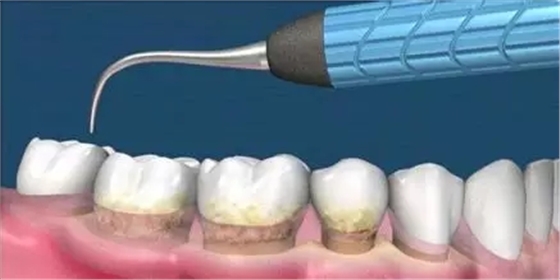

這是牙周病常規(guī)的治療方法,清除或控制臨床炎癥和致病因素,去除病因,消除炎癥。包括口腔衛(wèi)生宣教、充填齲洞、口腔潔治刮治、牙體牙髓治療、咬合調(diào)整、去除不良修復(fù)體、藥物治療(輔助手段,局部用藥效果好)、拔除治療效果不佳的牙周病患牙等。

牙周炎發(fā)展到一定階段時(shí),僅采用基礎(chǔ)治療難以取得較好療效,必須通過適時(shí)而合宜的手術(shù)治療挽救患牙,才能保持牙周組織健康,延長患牙在口腔內(nèi)的壽命,維持牙列的完整性,促進(jìn)全身健康。其手段包括齦下刮治、根面平整、牙周翻瓣術(shù)、牙齦切除術(shù)、牙周夾板固定術(shù)等。